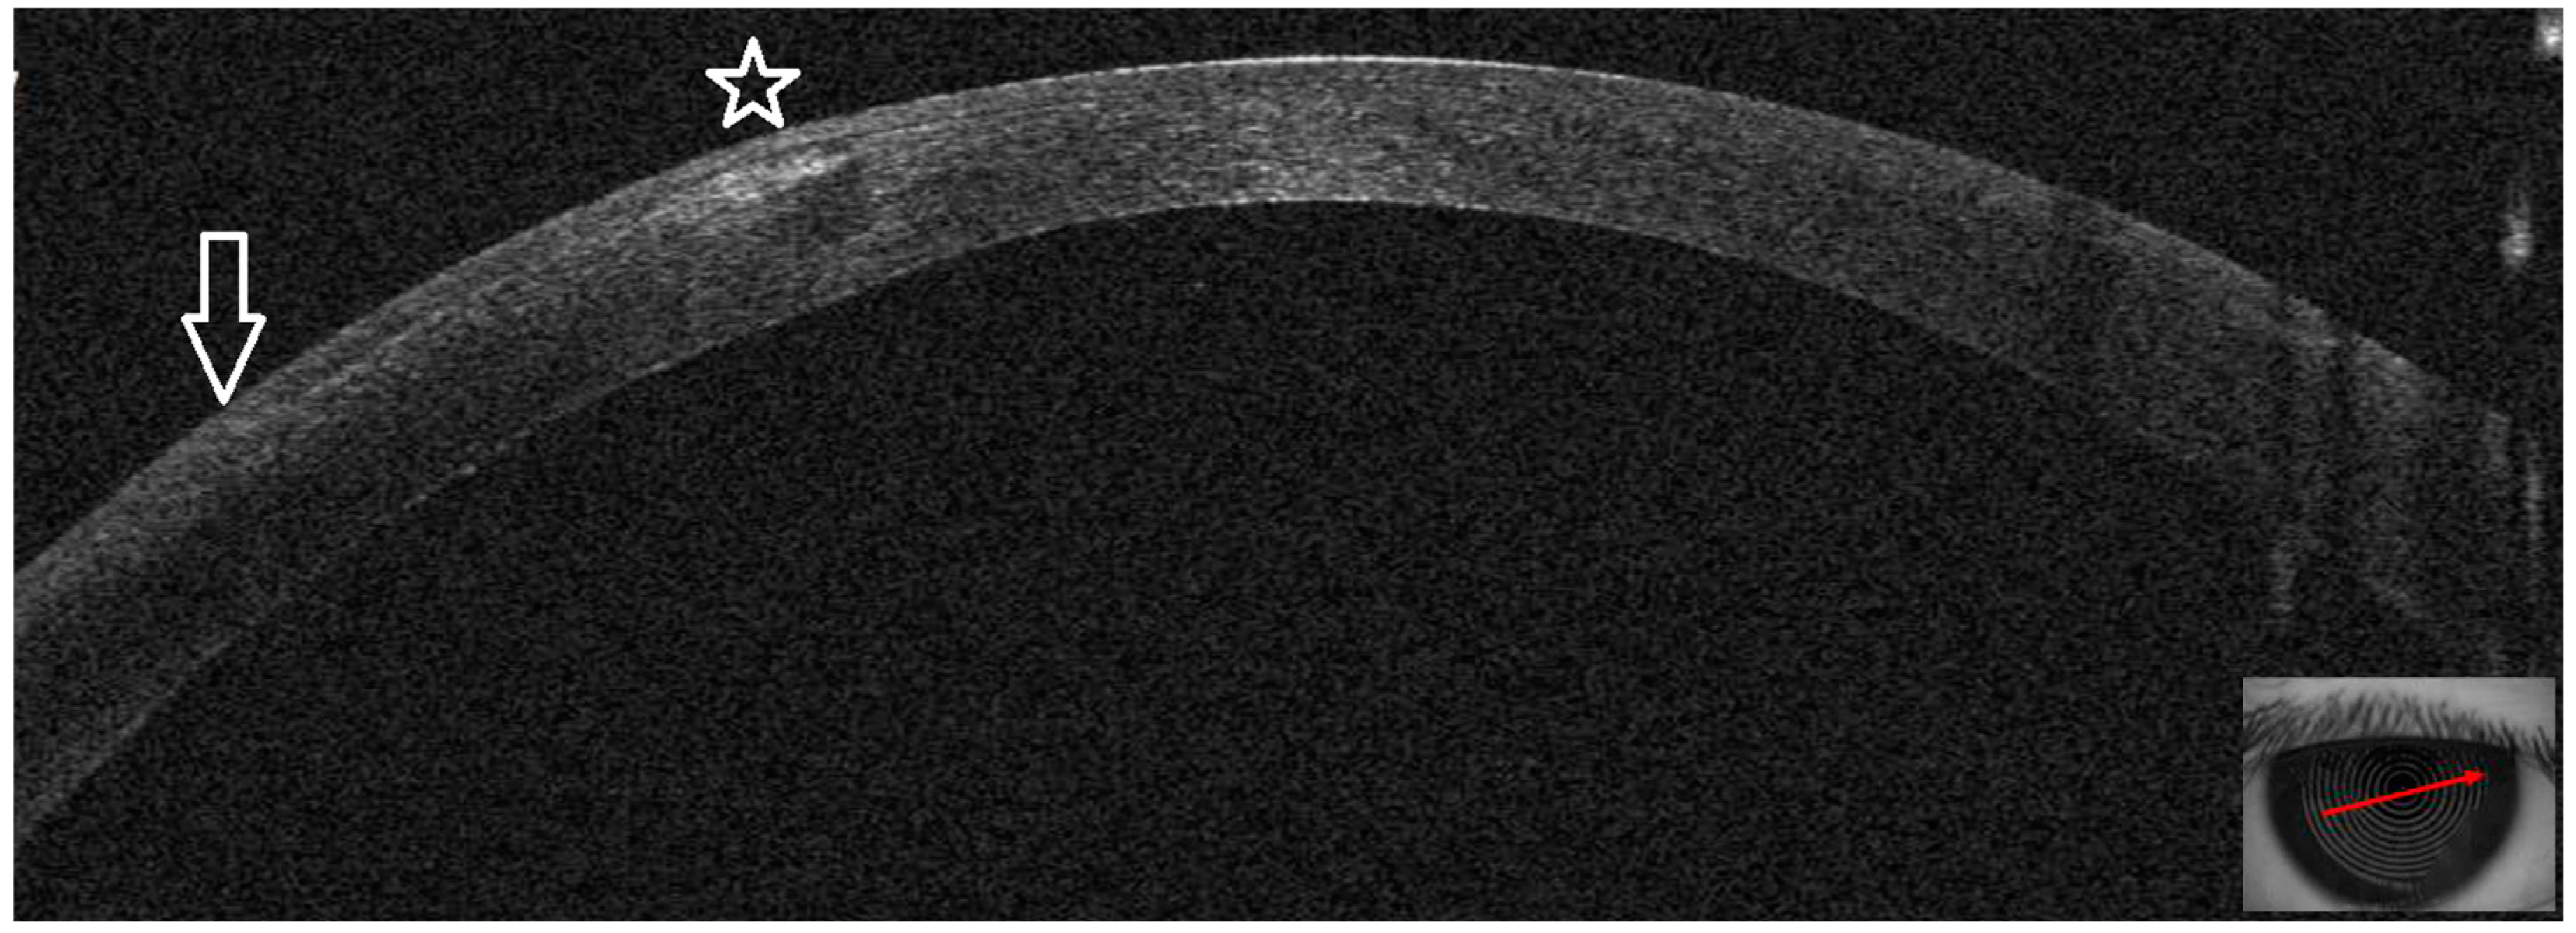

3.1. Patient #1